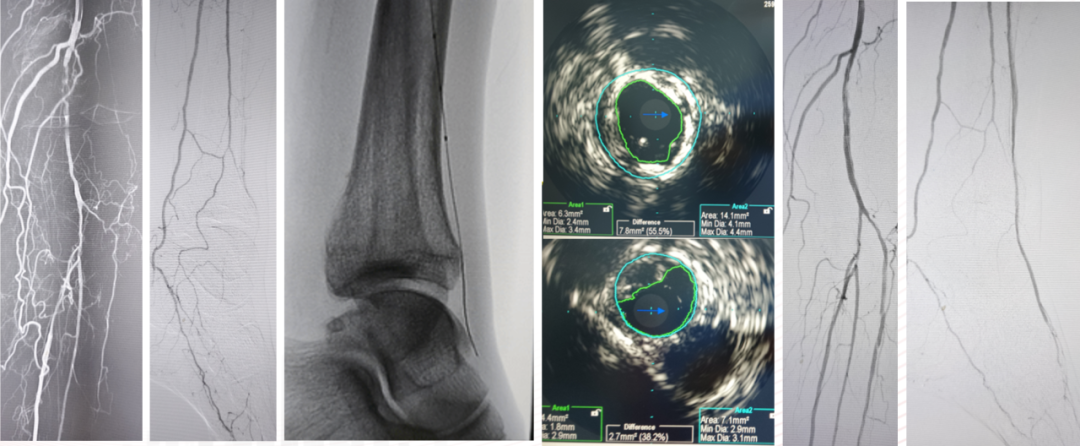

Knuckle技术通过导丝成袢快速通过长段闭塞,但部分术者担心其导致导丝进入假腔。实际上,借助血管内超声(IVUS)观察可见,Knuckle后导丝位置多样。

Case 1:胫前动脉长段闭塞,导丝成袢后通过,IVUS显示大部分位于假腔,但血流仍可维持。

Case 2:类似病变,成袢后导丝全程位于真腔,仅局部转弯处有夹层形成。